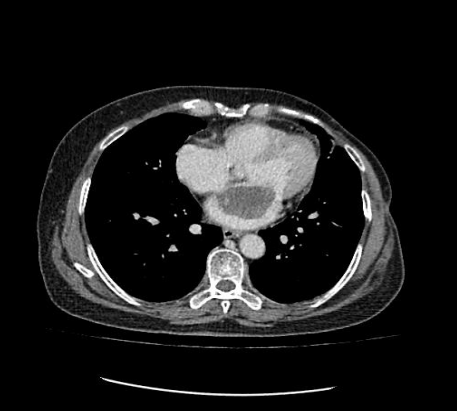

通訊員許欣報(bào)道:近日,我院心胸外科、麻醉科、手術(shù)室通力合作,為一名身患左房粘液瘤患者成功實(shí)施了胸腔鏡輔助下微創(chuàng)左房粘液瘤切除術(shù)。

患者為一名57歲的女性,心慌、胸悶的癥狀已有一年多,一直以為是“感冒”而沒(méi)放在心上。最近經(jīng)人介紹到我院檢查,經(jīng)心臟超聲檢查發(fā)現(xiàn)左心房上長(zhǎng)了一個(gè)雞蛋大小的黏液瘤。雖說(shuō)是良性的,但生長(zhǎng)位置在二尖瓣口,如果黏液瘤碎片或瘤體表面血栓脫落,可發(fā)生體循環(huán)或肺循環(huán)的栓塞,隨時(shí)有猝死的危險(xiǎn)。以往此類(lèi)疾病必須通過(guò)傳統(tǒng)胸部正中切口實(shí)施手術(shù),病人術(shù)后要經(jīng)過(guò)3-6個(gè)月左右的恢復(fù)期,患者創(chuàng)傷大、恢復(fù)慢、出血較多、切口瘢痕明顯、心理負(fù)擔(dān)重,無(wú)論是對(duì)身體還是心理都是一次嚴(yán)重創(chuàng)傷。為患者實(shí)施全胸腔鏡技術(shù)摘除左心房黏液瘤手術(shù),在不破壞患者破壞胸骨穩(wěn)定性的前提下,只需在患者胸壁上開(kāi)2個(gè)“鑰匙孔”樣大小觀察孔和1個(gè)4cm的操作孔即可進(jìn)行手術(shù),最大限度減少術(shù)后疼痛和創(chuàng)傷,縮短術(shù)后恢復(fù)時(shí)間。